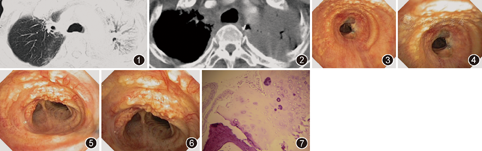

患者男,59岁,因"食道癌术后6年,顽固性咳嗽5年"于2010年3月15日入院。2004年2月因"食道中段癌"在江苏省肿瘤医院行"食道癌根治术",术后病理报告:鳞癌2级,累及黏膜下层,上下切缘阴性,癌旁淋巴结及胃左淋巴结阴性,术后恢复良好,但有轻微的饮水呛咳,改变饮食习惯后渐减轻。1年后出现咳嗽,咳白色黏痰伴痰中带血,声音嘶哑,喉镜检查示双侧声带麻痹,胸部CT发现左气管食管沟肿大淋巴结约2.5 cm×2.5 cm,考虑肿瘤复发,于2005年8月开始行三维适形放疗1个疗程,总剂量为6800 cGy,随后给予"奥沙利铂+甲酰四氢叶酸钙+5-氟尿嘧啶"方案化疗5个疗程,患者声嘶及饮水呛咳有所好转,纵隔淋巴结明显缩小,但咳嗽一直持续存在。曾辗转于省内多家三级医院,均被诊断为"放射性气管炎、放射性肺炎、胃食管反流性咳嗽等",给予糖皮质激素、抗感染及抗反流治疗,无明显效果。咳嗽症状近1年来明显加重,伴胸闷、气喘,偶有痰中带血。既往无刺激性气体及粉尘接触史,不吸烟,无传染病史,无家族性疾病及遗传病史。入院后体格检查无明显阳性体征,复查胸部CT示纵隔内胸腔胃影,未见异常软组织影及肿大淋巴结,气管支气管通畅,气管下段稍变形,双上肺纤维索条影和斑片状肺实变影,可见支气管充气征(图1,图2)。气管镜检查示双侧声带麻痹,声门紧闭,气管中下段黏膜表面密布大小不等的黄色结节(直径为2~5 mm),尤以前壁和侧壁为主,结节突入管腔,部分融合,质硬如鹅卵石样(图3,图4,图5,图6),采用大号鳄嘴钳夹取数块病变组织送检。病理结果示气管黏膜完整,上皮轻度增生伴鳞状化生,黏膜下可见软骨组织,局灶钙化(图7),病理诊断:骨化性气管支气管病(tracheobronchopathia osteochondroplastica,TO)。经糖皮质激素、抗感染及平喘化痰等对症治疗后,症状好转出院。2010年6月因肺部感染导致呼吸衰竭,经抢救无效而死亡。